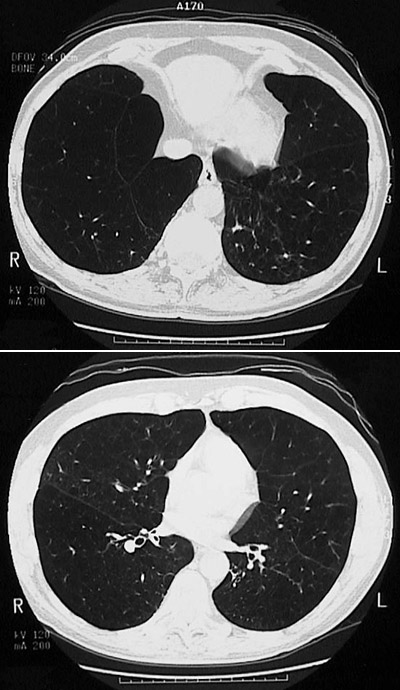

The chest CT scan views here in "lung window" demonstrate large lucencies with panlobular emphysema.